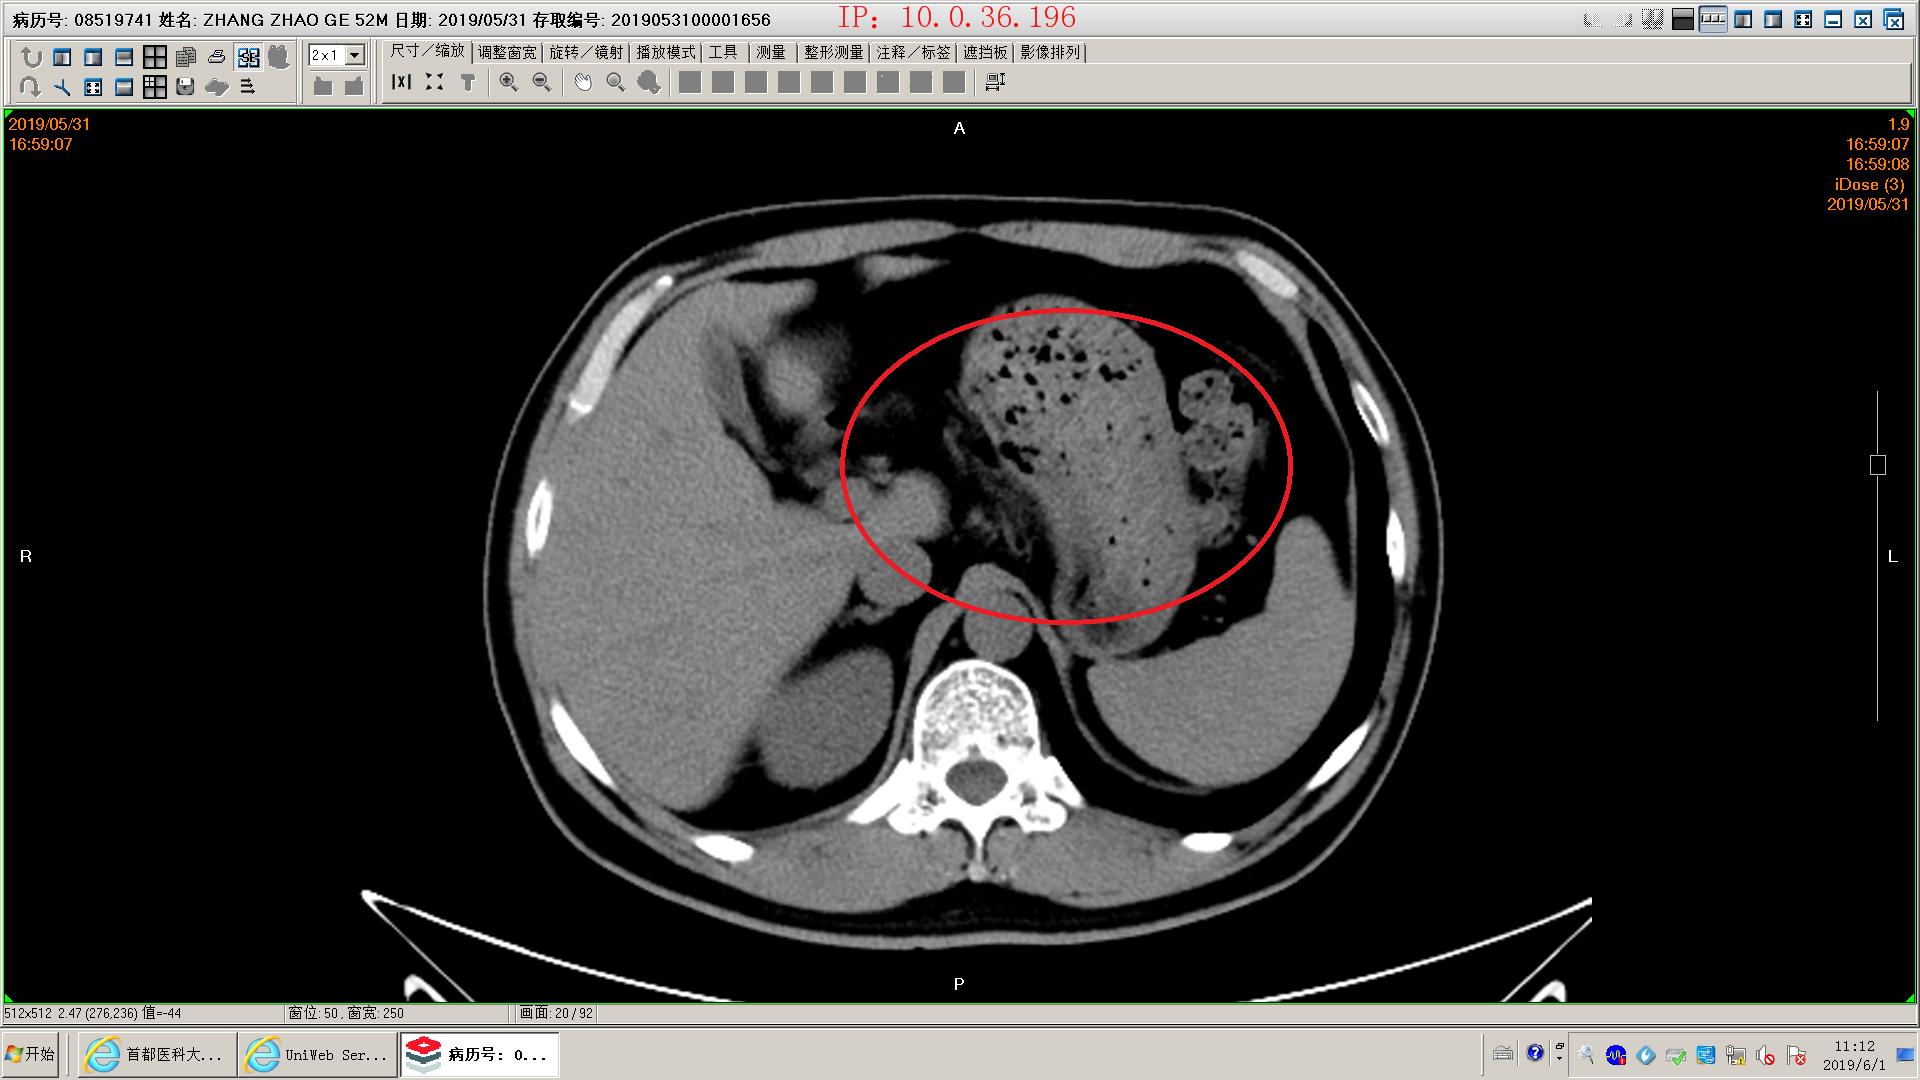

下面是一例胆源性胰腺炎影像学和化验表现,这个病人没有脏器功能不全,胰腺坏死不明显,周围没有明显积液,还不是重症胰腺炎。虽然有可疑胆管结石,但是没有黄疸,我们会在做核磁mrcp证实一下结石的位置。患者胃里面有一些残存的食物,我们会用胃管做胃肠减压,有助于胃肠道休息恢复;肠道里面积存的粪便也比较多,肠鸣音听不到,通过肥皂水灌肠促进肠道蠕动排除,有助于胃肠道功能恢复。然后给予生长抑素抑制胰酶分泌,禁食水补液,消炎治疗。

可疑胆总管结石

胰腺模糊渗出,坏死不明显

胰腺间隙模糊

胃内有残余食物

肠道积存大量粪便